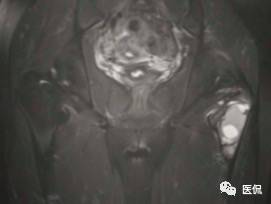

患者资料:男,26岁,左髋部疼痛10余天,无明显诱因出现左侧髋部疼痛,影像行走,夜间疼痛尤其明显。

影像资料:

(3)MRI ABC的特征为鼓囊状的膨胀性破坏,呈单囊或由低信号的间隔分隔成大小不等的多囊。因血细胞和血浆的分离和沉淀,囊内可见液-液平面。在T2WI上,液面上层为高信号,下层为低信号;T1WI上则相反,上层为低信号,下层为偏高信号。液-液平面是ABC较特征的征象。增强检查低信号的纤维间隔呈环形强化。继发性动脉瘤样骨囊肿可在其原发病灶内有液-液平。

【诊断要点】发生于青少年长骨干骺端偏心膨胀的溶骨性病变,MRI检查病灶内见有液-液平征象时应首先考虑为动脉瘤样骨囊肿。